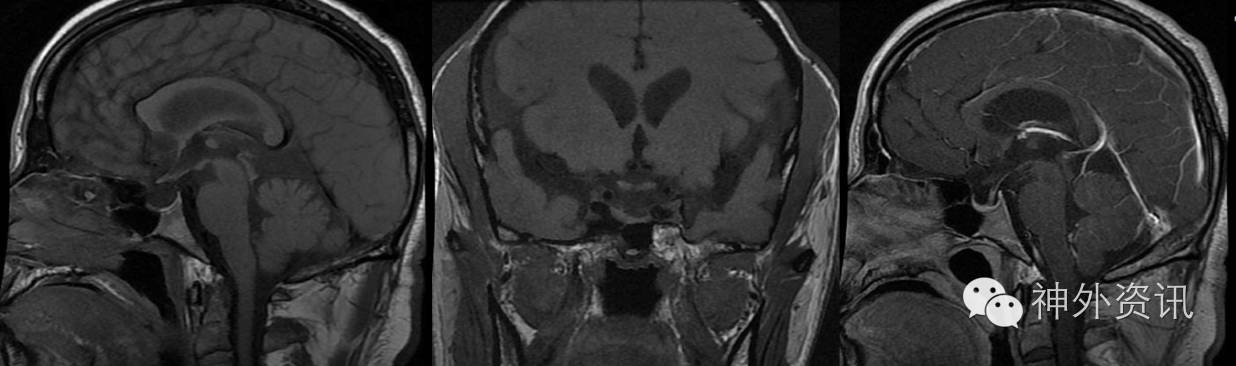

入院行垂体MRI检查提示垂体变薄,两侧不对称,垂体柄偏斜,垂体信号及强化未见异常,考虑空蝶鞍趋势。同时见右侧外侧裂区域液性信号影,脑池扩大?(图1)

图1. 垂体MRI检查提示垂体变薄,两侧不对称,垂体柄偏斜,垂体信号及强化未见异常,脑室轻度扩大。